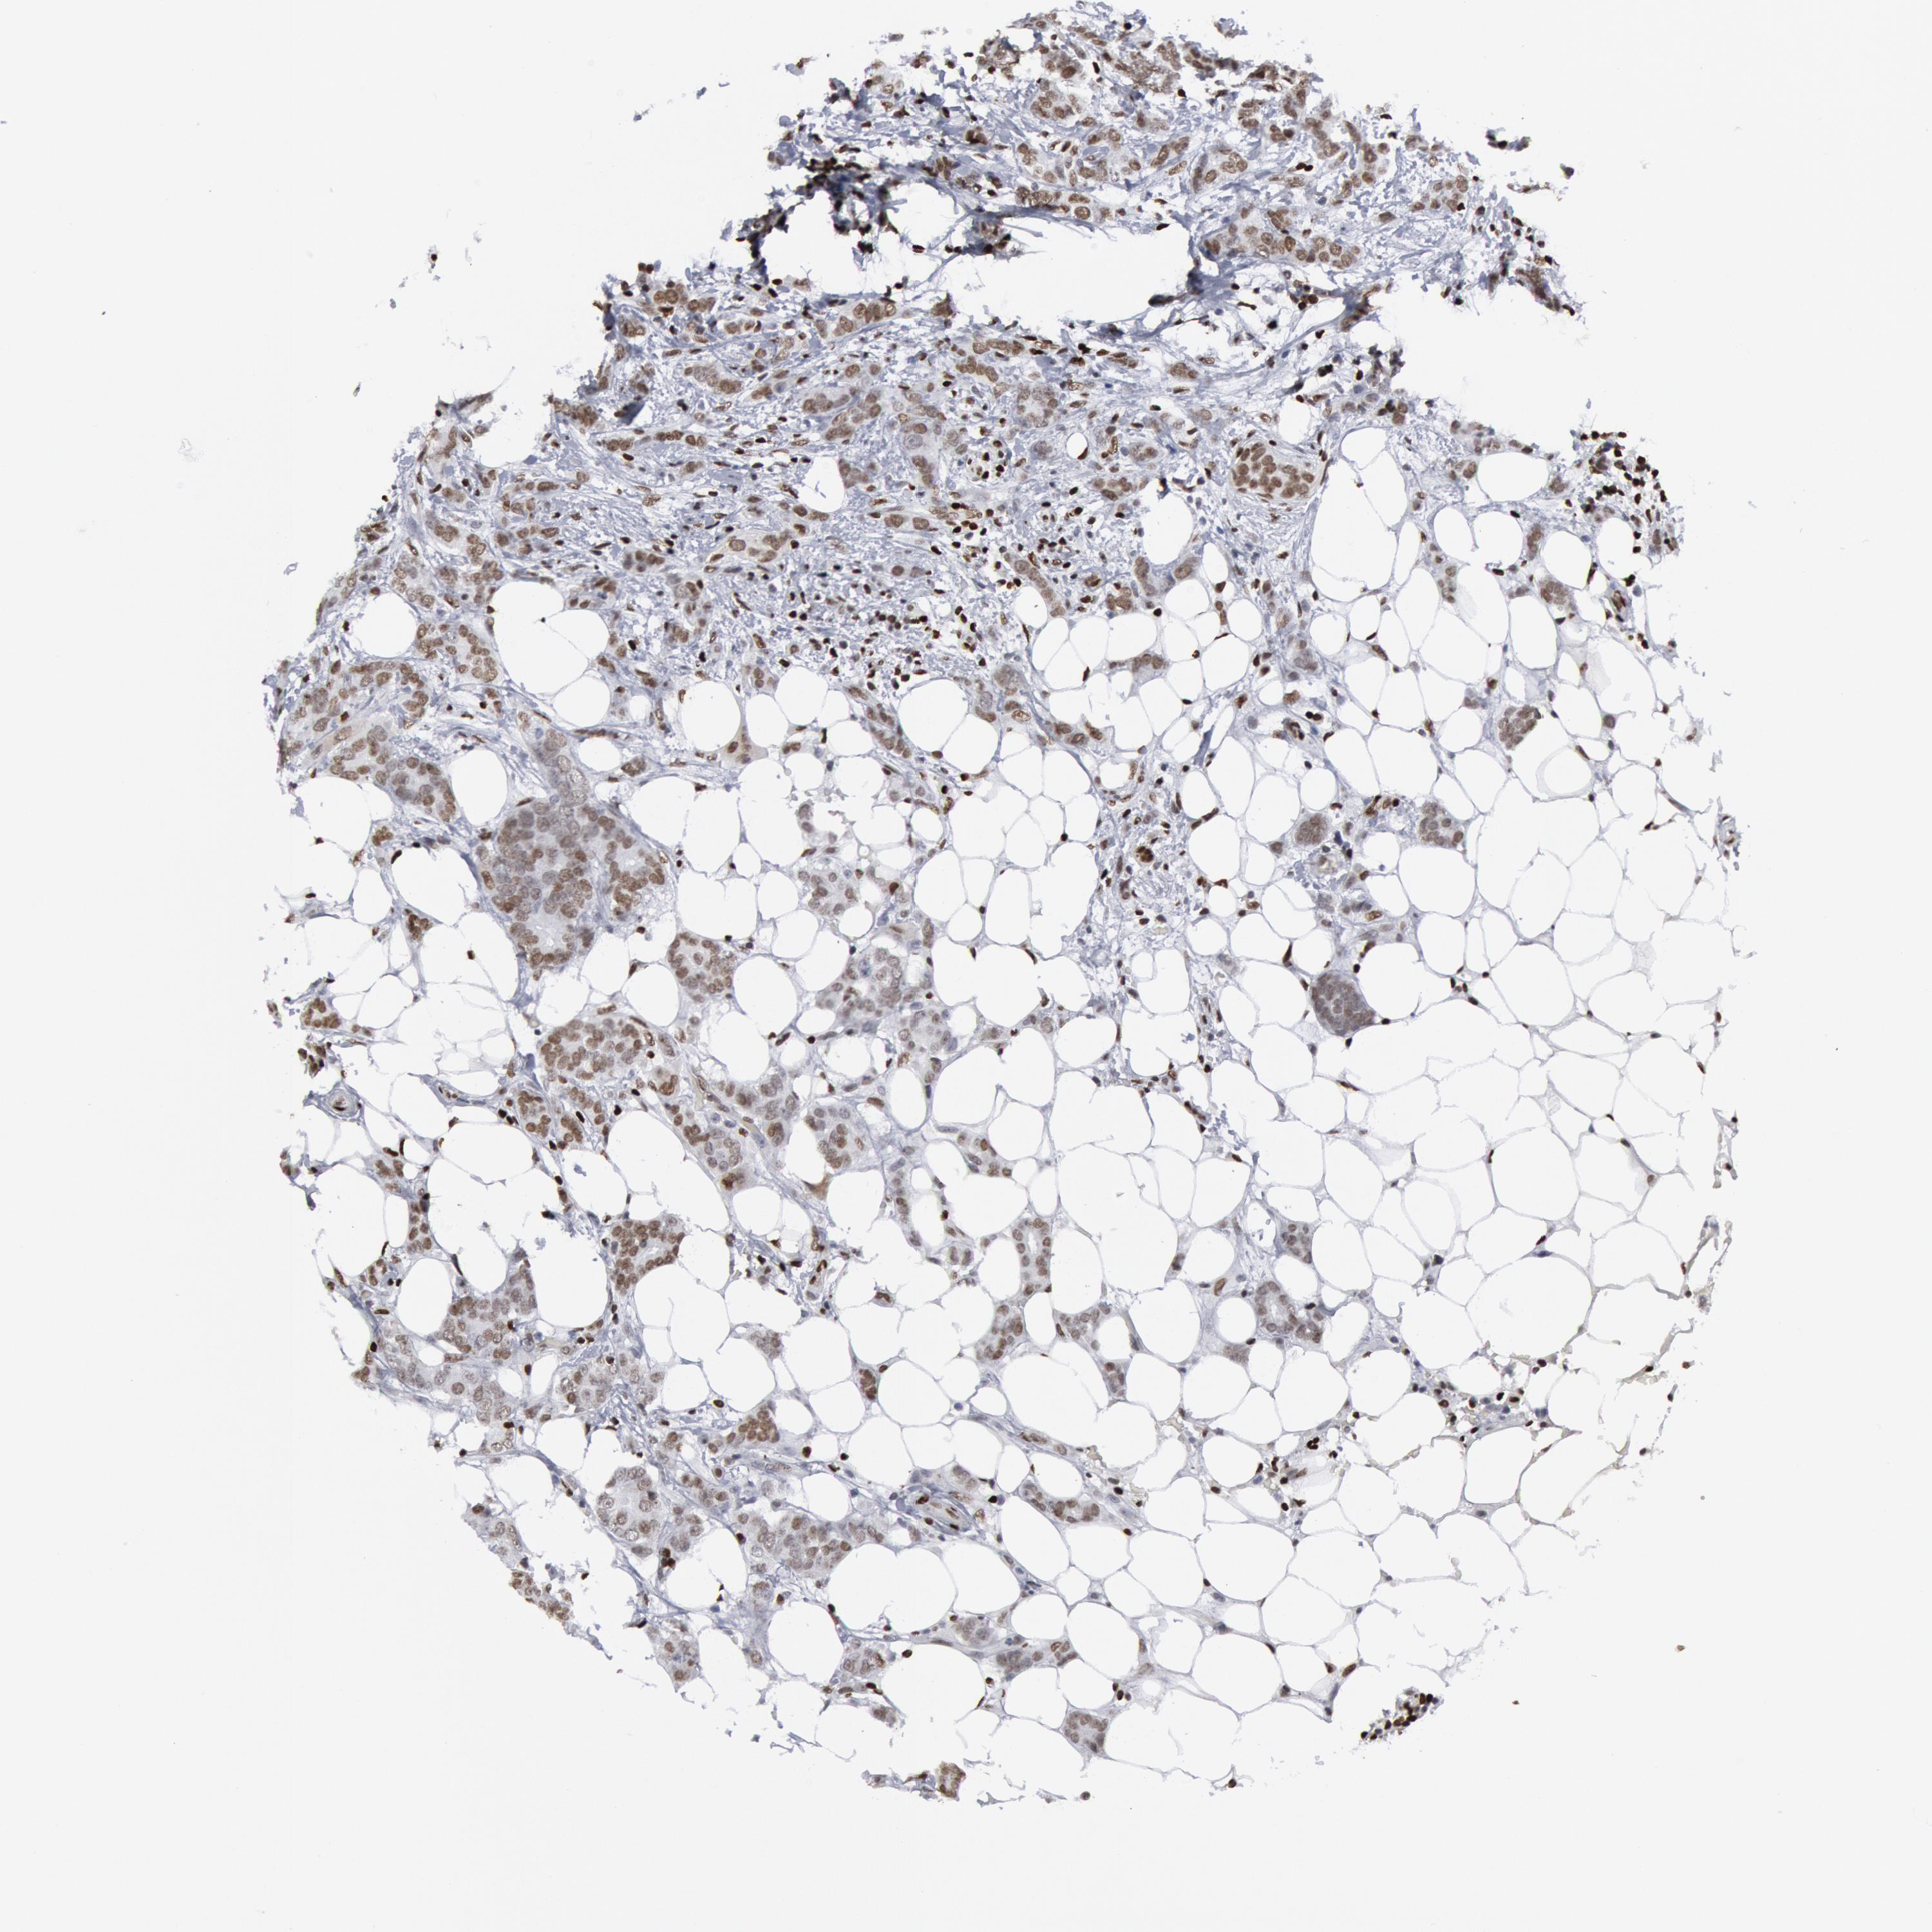

CANCER BREAST CANCER Show tissue menu

BRCA TCGA BRCA VALIDATION PROTEIN EXPRESSION

Breast cancer

Human cancer